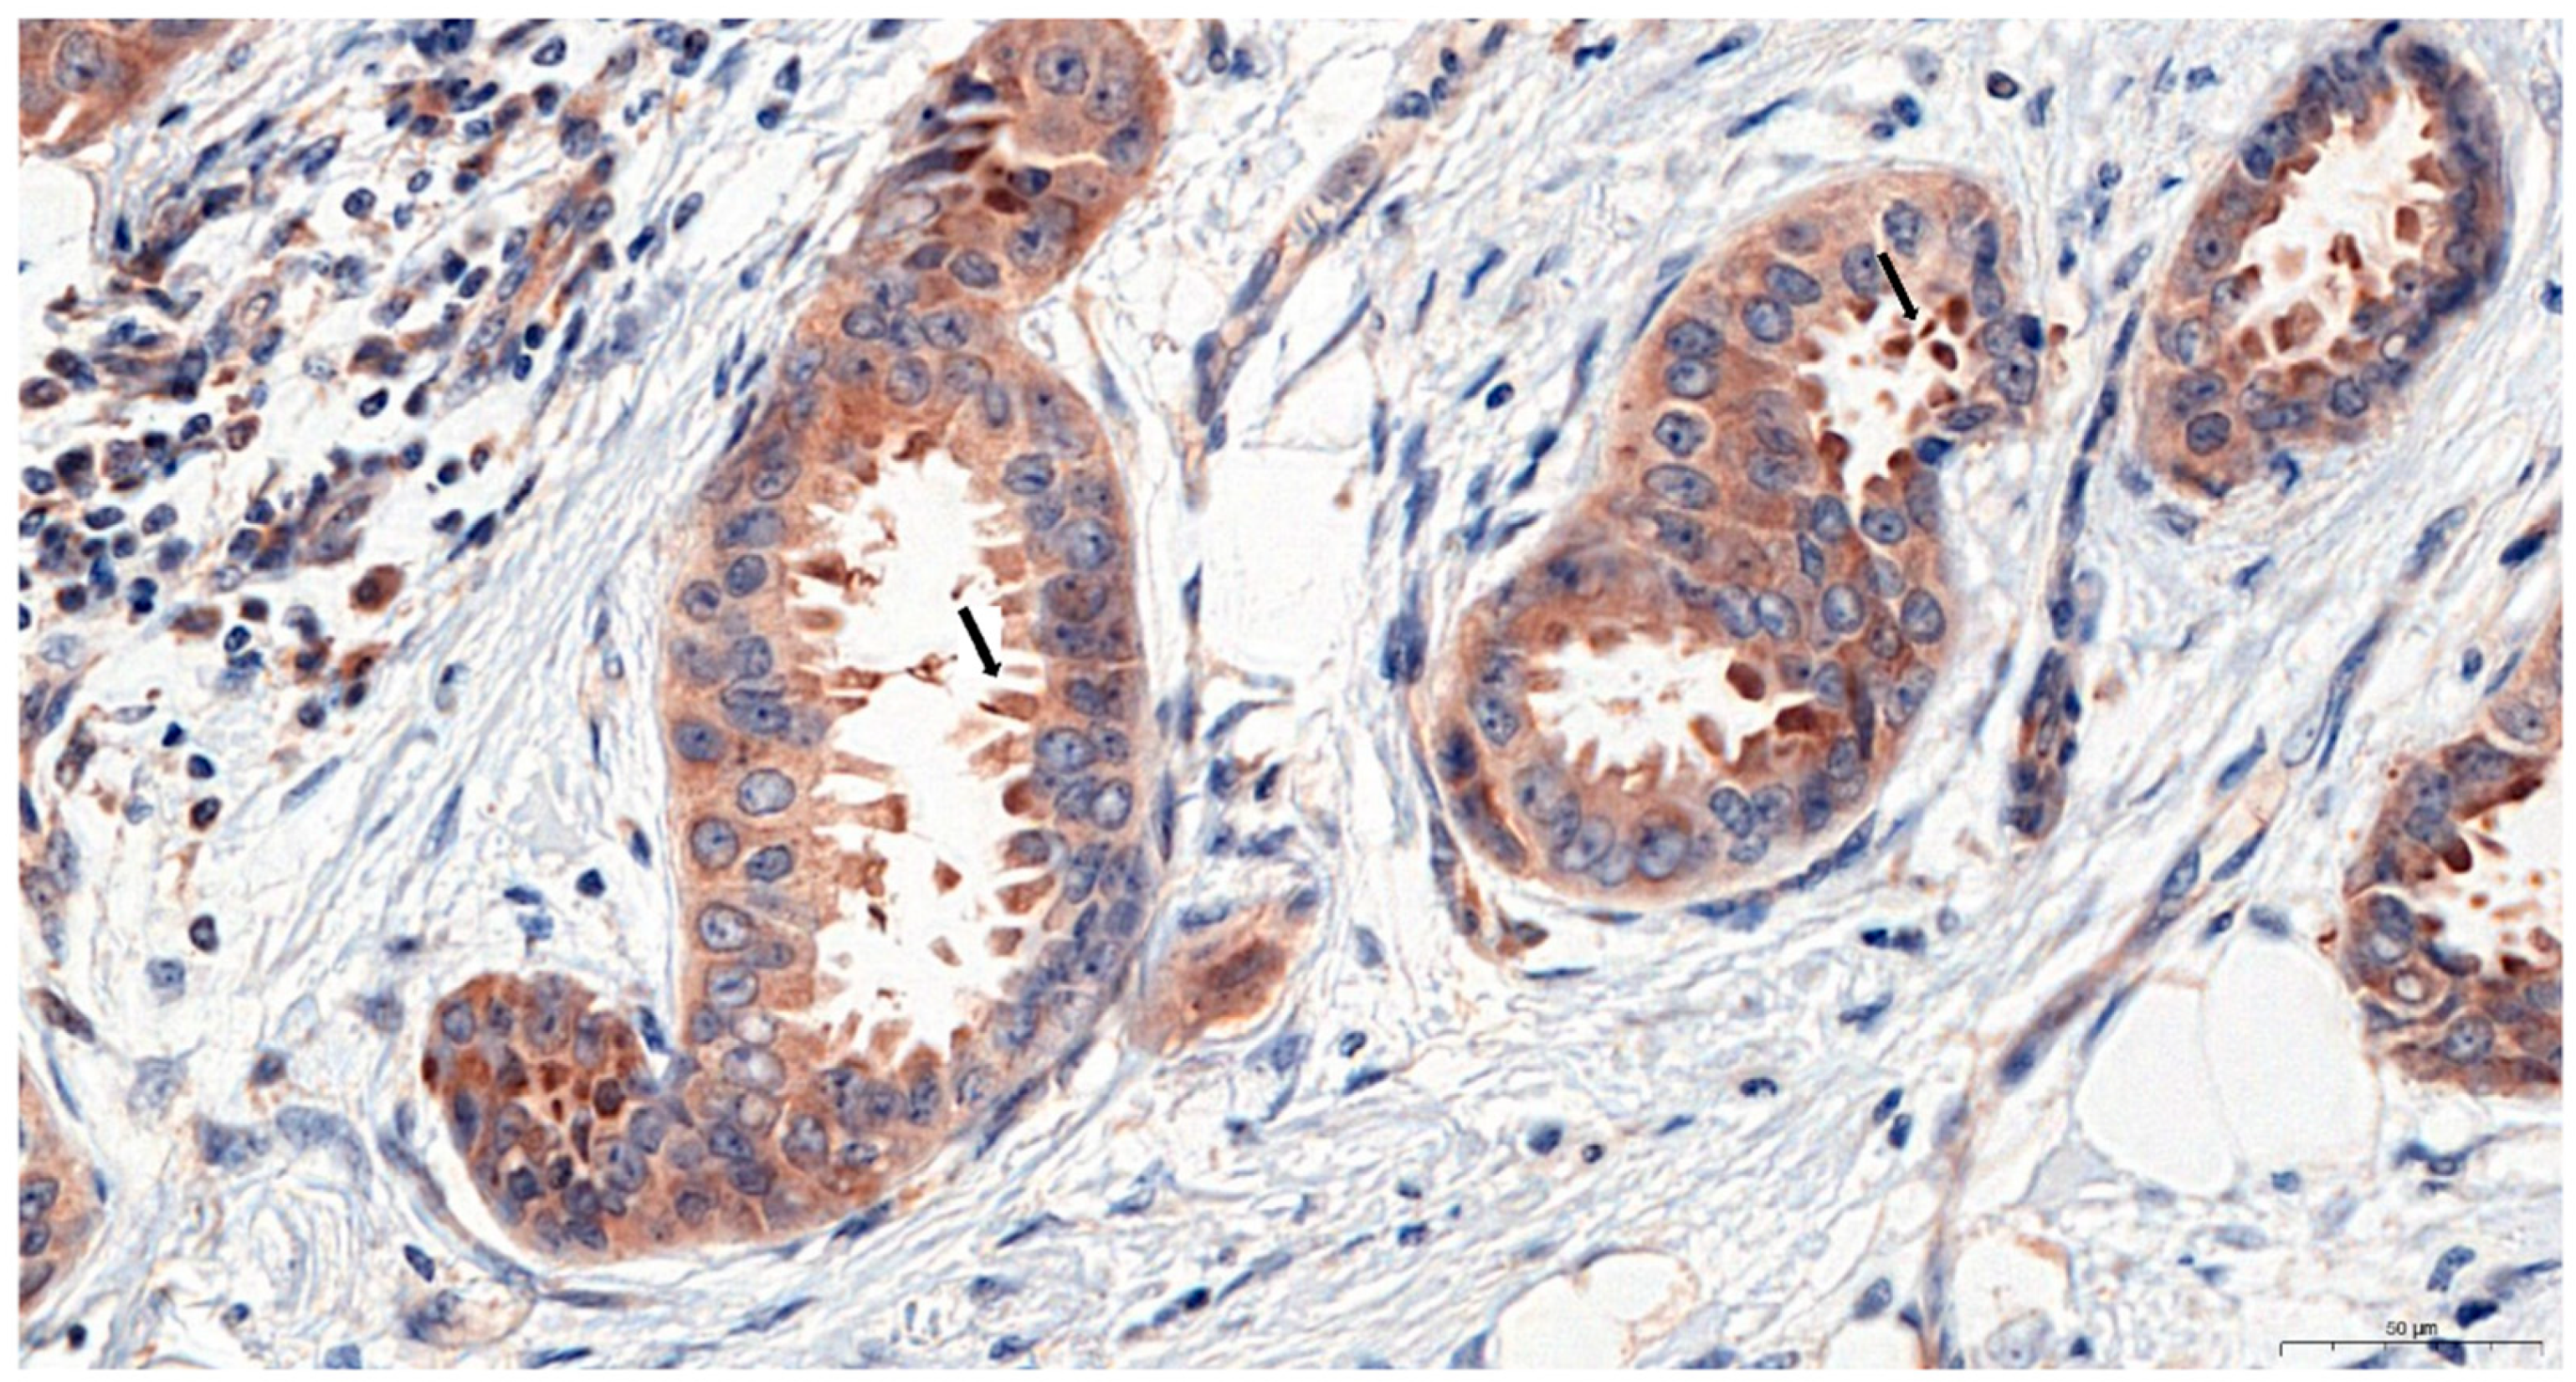

2.1. Immunohistochemical (IHC) Detection of Irisin Expression in Tissue Microarrays (TMAs) with Different Breast Cancer Types